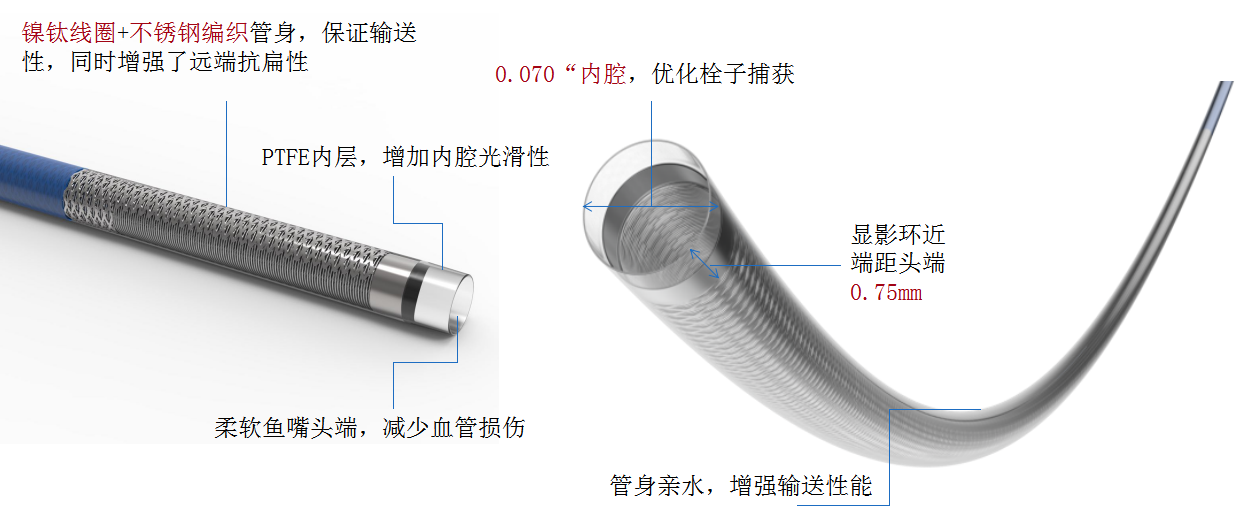

中间导管配合在长鞘和小球囊的配合下穿过迂曲夹层的颈内动脉。

· 串联闭塞如何快速建立颅内的治疗通路

· 如何避免近端颈动脉再次栓塞

· 如何缩短复流所需时间